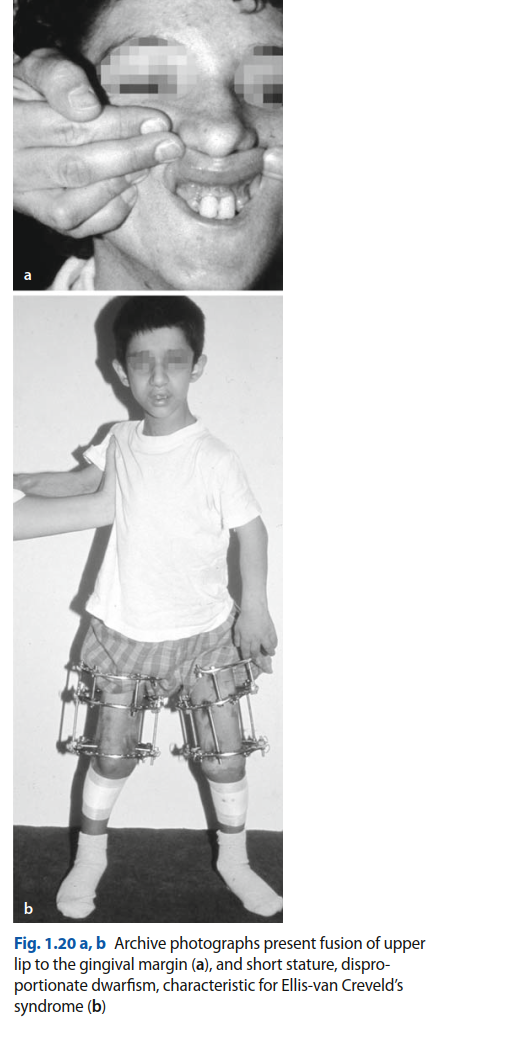

تُعد متلازمة إليس فان كريفيلد (Ellis-Van Creveld Syndrome)، المعروفة أيضًا باسم خلل التنسج الغضروفي الجلدي الظاهري (Chondroectodermal Dysplasia)، حالة وراثية نادرة ومعقدة تتطلب فهمًا عميقًا ورعاية متخصصة. بصفتي الأستاذ الدكتور محمد هطيف، استشاري جراحة العظام والعمود الفقري الرائد في صنعاء، أقدم لكم هذا الدليل الشامل والمفصل لمساعدتكم على فهم هذه المتلازمة، بدءًا من أسبابها وأعراضها وصولًا إلى خيارات التشخيص والعلاج المتاحة، مع التركيز على الجوانب العظمية والفموية التي تمثل تحديًا كبيرًا للمرضى وعائلاتهم.

متلازمة إليس فان كريفيلد هي اضطراب جيني نادر يؤثر على أجزاء متعددة من الجسم، وخاصة الهيكل العظمي والفم والقلب. سُميت المتلازمة بهذا الاسم نسبة إلى الطبيبين ريتشارد إليس وسيمون فان كريفيلد اللذين وصفاها لأول مرة عام 1940. تُصنف هذه المتلازمة ضمن عائلة اضطرابات خلل التنسج العظمي الغضروفي، وتتميز بمجموعة فريدة من العلامات السريرية التي تختلف في شدتها من شخص لآخر.

- قصر القامة وقصر الأطراف: يعاني الأطفال المصابون من قصر قامة ملحوظ. يتميز قصر الأطراف بكونه "ميزوميليك" (mesomelic) و"أكروميليك" (acromelic)، مما يعني أن الأجزاء الوسطى (الساعدين والساقين) والبعيدة (اليدين والقدمين) من الأطراف أقصر بشكل غير متناسب مقارنة بالأجزاء القريبة (الذراعين والفخذين).

- اندماج الحافة السنخية بالشفة: من السمات المميزة هو اندماج الحافة السنخية الأمامية للفك العلوي بالشفة العليا، مما يؤدي إلى تجويف فموي ضحل وقد يساهم في ظهور شق شفوي وسطي كاذب. هذا يقيد حركة الشفاه بشكل كبير ويجعل النظافة الفموية صعبة.

- يقوم الطبيب بفحص الطفل بحثًا عن العلامات المميزة للمتلازمة، مثل قصر القامة، وتعدد الأصابع في اليدين والقدمين، وتشوهات الركبتين، والمظاهر الفموية مثل الأسنان الوليدية وتضخم اللثة.